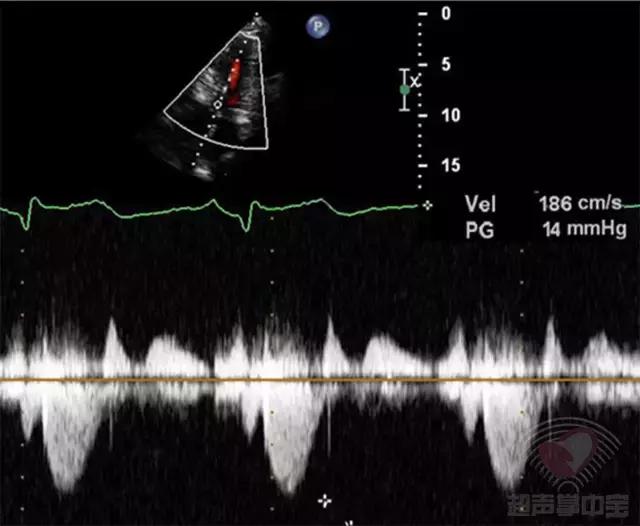

患者经皮经腔间隔心肌消融术后3天复查超声心动图(图3):CW:左室流出道最大瞬时流速和压差为:186cm/s,PG:14mmHg。

图3 非对称性肥厚型梗阻性心肌病:经皮经腔间隔心肌消融术后3天复查超声心动图心尖五腔心切面CW测左室流出道峰值流速186cm/s